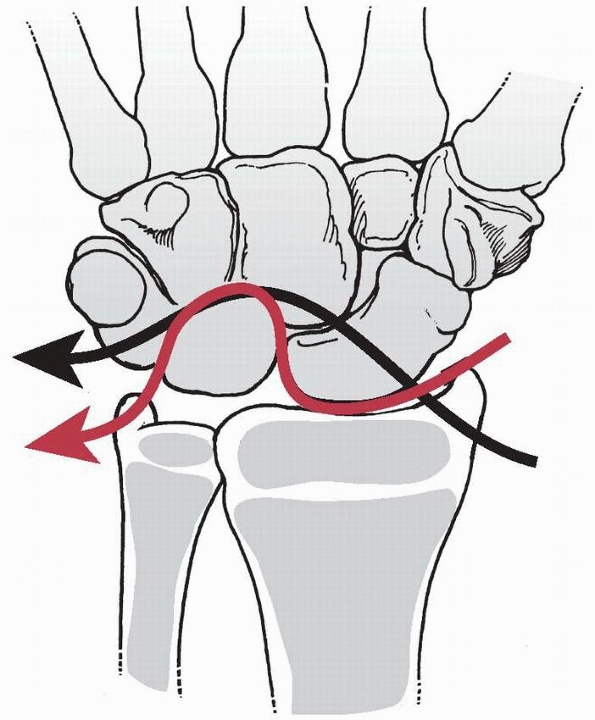

relatively protected within the hand. Considerable variation exists in

the relative mobility of the metacarpals through the carpometacarpal

(CMC) joints. The index and long rays have minimal CMC joint motion (10

to 20 degrees). In contrast, the ring and small rays possess more

motion (30 to 40 degrees), and the thumb CMC joint has universal motion.

The metacarpal geometry and composition predispose the metacarpal neck

to injury. The distal metacarpal angles as it approaches the MCP joint,

and the cortical bone within the subcondylar fossa is relatively thin,

which creates a vulnerable area susceptible to injury.

all cause fractures of the metacarpal. Contact sports or striking an